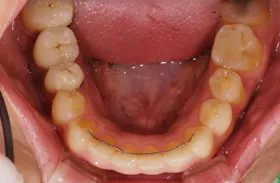

■治療前:奥歯が無いため噛み合わせが深く下の歯が全く見えない

噛み合わせが低いため全体的に歯が削れている

■治療後:下顎 左下5・6番、右下4・6番にインプラント治療

その他の歯に補綴治療をしたことにより、奥歯もしっかりと咬むことができ、奥歯ができたことにより噛み合わせも上がって下の歯も見えるようになり、審美的にも改善された

| 主訴 | 歯科治療をしても歯がすぐに欠けてしまう 奥歯が無いため、奥歯で咬めない |

|---|---|

| 治療方法 | インプラント治療 + 補綴治療 |

| 治療期間 | 約1年 |

| 通院回数等 | 約20回 |

| 費用 | 約250万円(税込) |

| リスク・副作用 | 術後の腫れ・痛み |